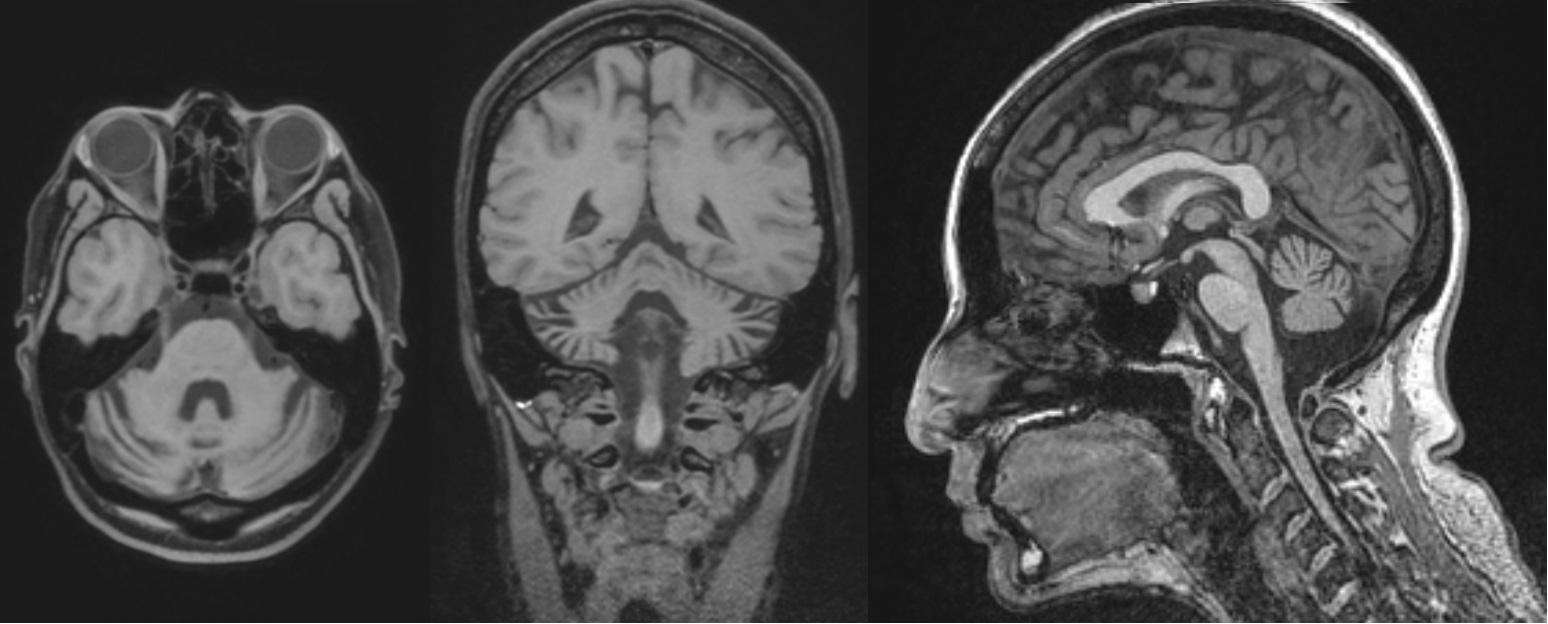

Results: The patient developed progressive issues with speech production beginning at age 28 which advanced over months. The following year she developed gait issues which resulted in falls within a year of onset, and difficulty coordinating her right upper extremity. Neurologic examination at time of initial evaluation at our center, 19 months after symptom onset, was notable for a wide-based ataxic appearing gait, and she was unable to tandem walk due to unsteadiness. There was mild upper extremity ataxia and dysmetria, mild to moderate ataxia with heel-to-shin movements, and subtle parkinsonian features. Speech pathology evaluation revealed a slow speaking rate with inter word segmentation, revisions and restarts, apractic sound errors and a reduced range of prosodic variation, with slow but otherwise normal speech AMRs. MRI of the brain 19 months after symptom onset showed cerebellar atrophy with prominent involvement of the right greater than left cerebellar hemisphere [figure1] and corresponding hypometabolism was seen on FDG brain PET CT [figure2]. AP3B2 antibody was positive in serum and CSF on tissue immunofluorescence and cell binding assay. FDG body PET CT showed no evidence of malignancy. She noted improvements in mobility and balance four weeks after starting methylprednisolone and mycophenolate.

Figure 1